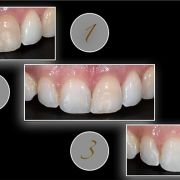

1- before non vital bleaching

2- after non vital bleaching, tooth still discolored!

3- after "inside out" composite layering

playing with composite opacities from inside out is very important to treat such a cases !